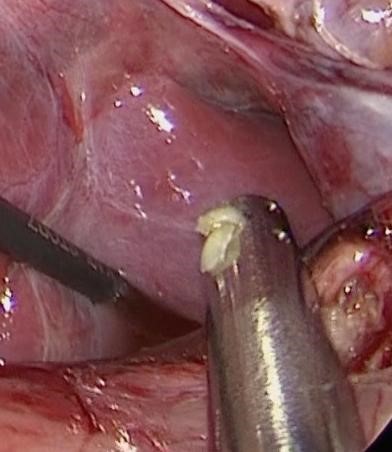

先天性胆道拡張症と診断された場合、手術(総肝管空腸吻合術)が必要です。

小児医療の拠点である名大病院で、新生児を含む重症・難治性疾患の外科治療に数多く携わる。特に肝胆膵疾患の経験が多く、2015年には東欧から来日した女児の先天性胆道拡張症再手術に成功。胸腔鏡・腹腔鏡を用いた侵襲度の低い内視鏡手術にも高い技量を持つ。将来の小児医療をさらに発展させるべく様々な角度から日々診療と研究を続けている。